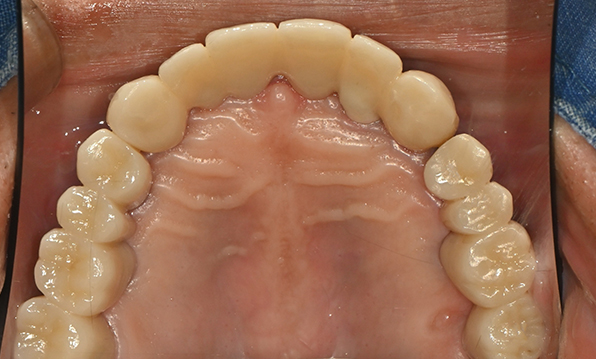

Full PlacementUsing a method of placing 8–9 implants in the maxilla and 8 implants in the mandible, this approach fully restores all 28 natural teeth, creating an oral environment most closely resembling

natural dentition. -